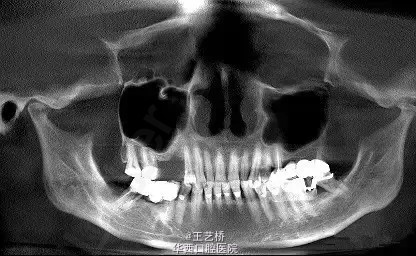

各式各样形态的上颌窦(一)

在进行上颌后牙区种植手术时,上颌窦形态是我们需要考虑吧的重要因素之一。今天收集了众多上颌窦的影像片,供大家交流学习。